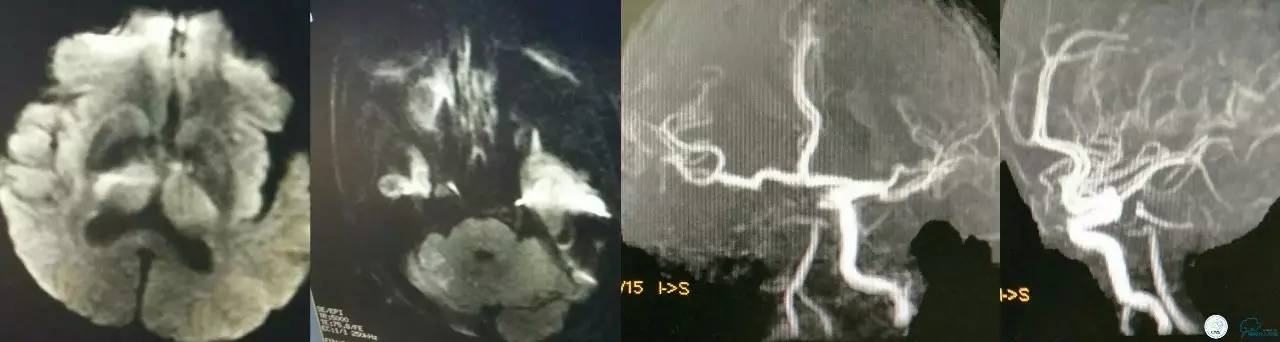

急诊MRI+MRA:右侧丘脑及小脑半球多发新鲜梗死病灶,右侧颈内动脉颅内段未见显影,基底动脉尖未见显影!

患者病情危重,责任血管:右侧颈内动脉?右侧大脑后动脉?